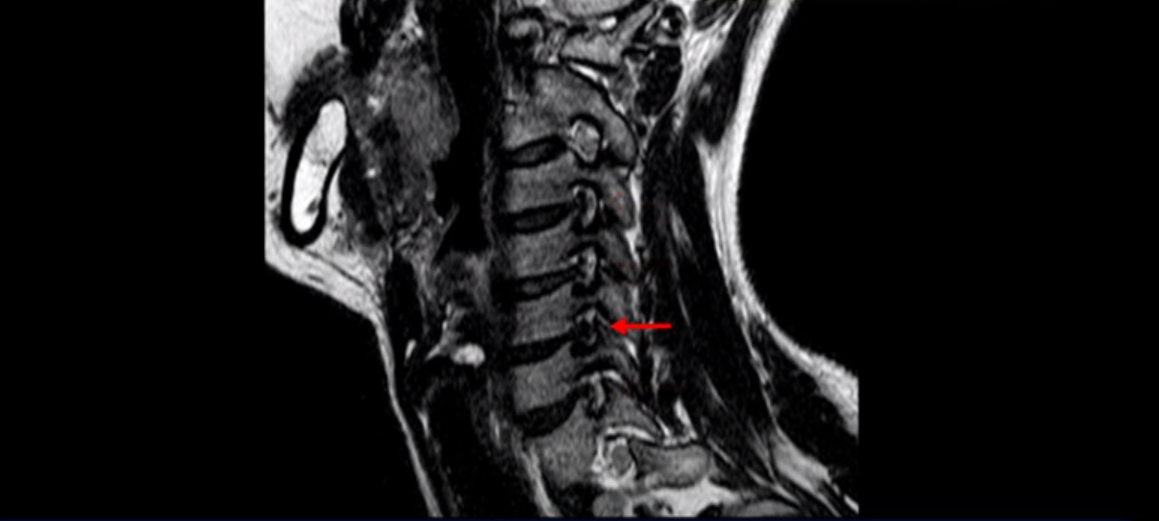

우선 이분 MRI를 보기 전에 이분 증상에 대해 말씀 드리면 오른쪽 팔저림과 방사통 및 어깨 통증이 있습니다. MRI를 보면 4번 5번에 디스크 파열이 보입니다.

밀려나온 디스크가 위로 타고 올라가 있는데 보시다시피 가운데로 밀려 나와 있습니다.

그래서 이게 오른쪽 통증의 원인일 수도 있고 아닐 수도 있습니다. 5번 6번은 왼쪽으로 밀려 나와있으니까 오른쪽 통증의 원인이 아닙니다.

그런데 이분 목을 보시면 여러 마디의 뼈가 퇴행이 진행되어 있습니다. 뼈가 깍두기처럼 각지고 예뻐야 하는데 끝이 조금씩 변형되어 뾰족하게 자라고 있습니다.

이런 게 협착을 일으킵니다. 그래서 우선 오른쪽 신경구멍 즉 추간공을 살펴보면 맨 위의 한마디를 빼고는 다 좁아져 있습니다.

특히 5번 6번 구멍이 가장 좁습니다. 이걸 협착이라고 합니다.

목 치료가 쉽다고 하는 것은 이러한 근육치료가 허리에 비해 훨씬 더 쉬운 겁니다. 목 근육이 허리 근육에 비해 훨씬 구조도 단순하고 치료하기도 쉽습니다. 또 목은 머리만 받치고 있기 때문에 허리에 비해 부담을 적게 받습니다. 그래서 치료하기가 훨씬 더 쉽고 빠른 겁니다. 이분 목 X-RAY를 보면 일자목이면서 커브도 매우 좋지 않습니다. 이런 일자목, 거북목 상태에서는 목 주변 근육이 만성적으로 굳어있고 뭉쳐 있을 가능성이 매우 높고 그러니까 만성적인 목 통증이 있는 겁니다. 이런 뭉치고 굳어있는 근육이 목뼈를 심하게 잡아당기면 신경 자극 증상이나 신경 눌림 증상이 생기기 쉽습니다.